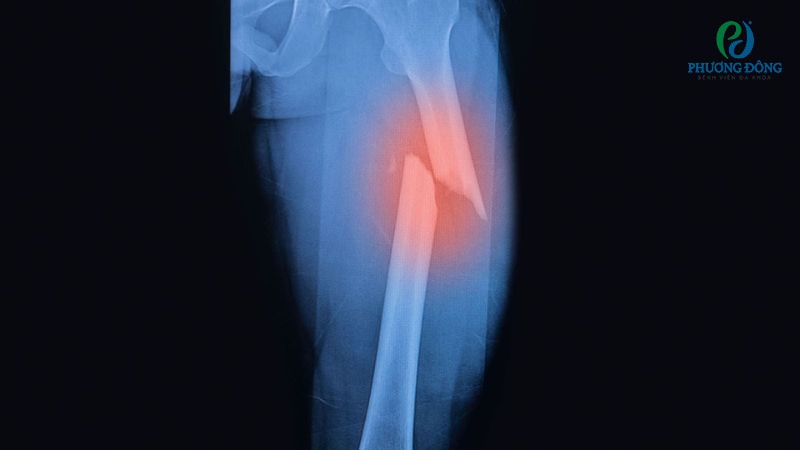

Gãy xương đùi

Gãy xương đùi chủ yếu xảy ra ở phần trên, nơi kết nối với xương chậu để tạo thành khớp háng. Một số dạng chấn thương thường gặp bao gồm gãy chỏm xương đùi, gãy cổ xương đùi và gãy liên mấu chuyển xương đùi.

Tuy xương đùi thuộc nhóm xương chắc khỏe nhất trong cơ thể, nhưng vẫn có thể đứt gãy khi té ngã mạnh hoặc tai nạn giao thông nghiêm trọng. Tỷ lệ chấn thương tăng cao ở nhóm bệnh nhân trên 65 tuổi, phụ nữ mãn kinh do thường đi kèm tình trạng loãng xương.